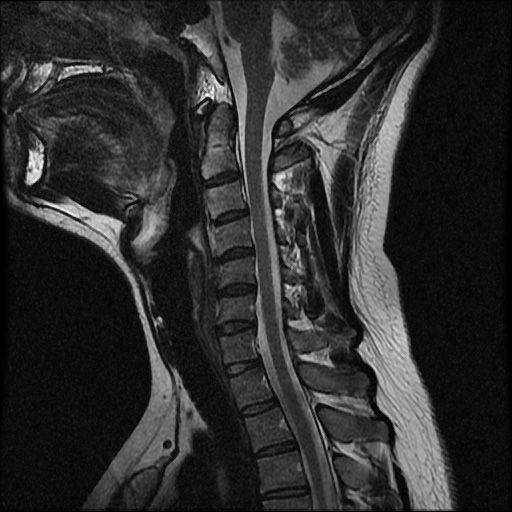

이 MRI 사진은 21년도 사고 당시 찍은 MRI 사진 입니다. 확인 부탁드립니다~

전체 mri를 다 봐여겠지만 보여주신 mri 컷에서는 의미있는 경추 디스크탈출이 보이지 않습니다.